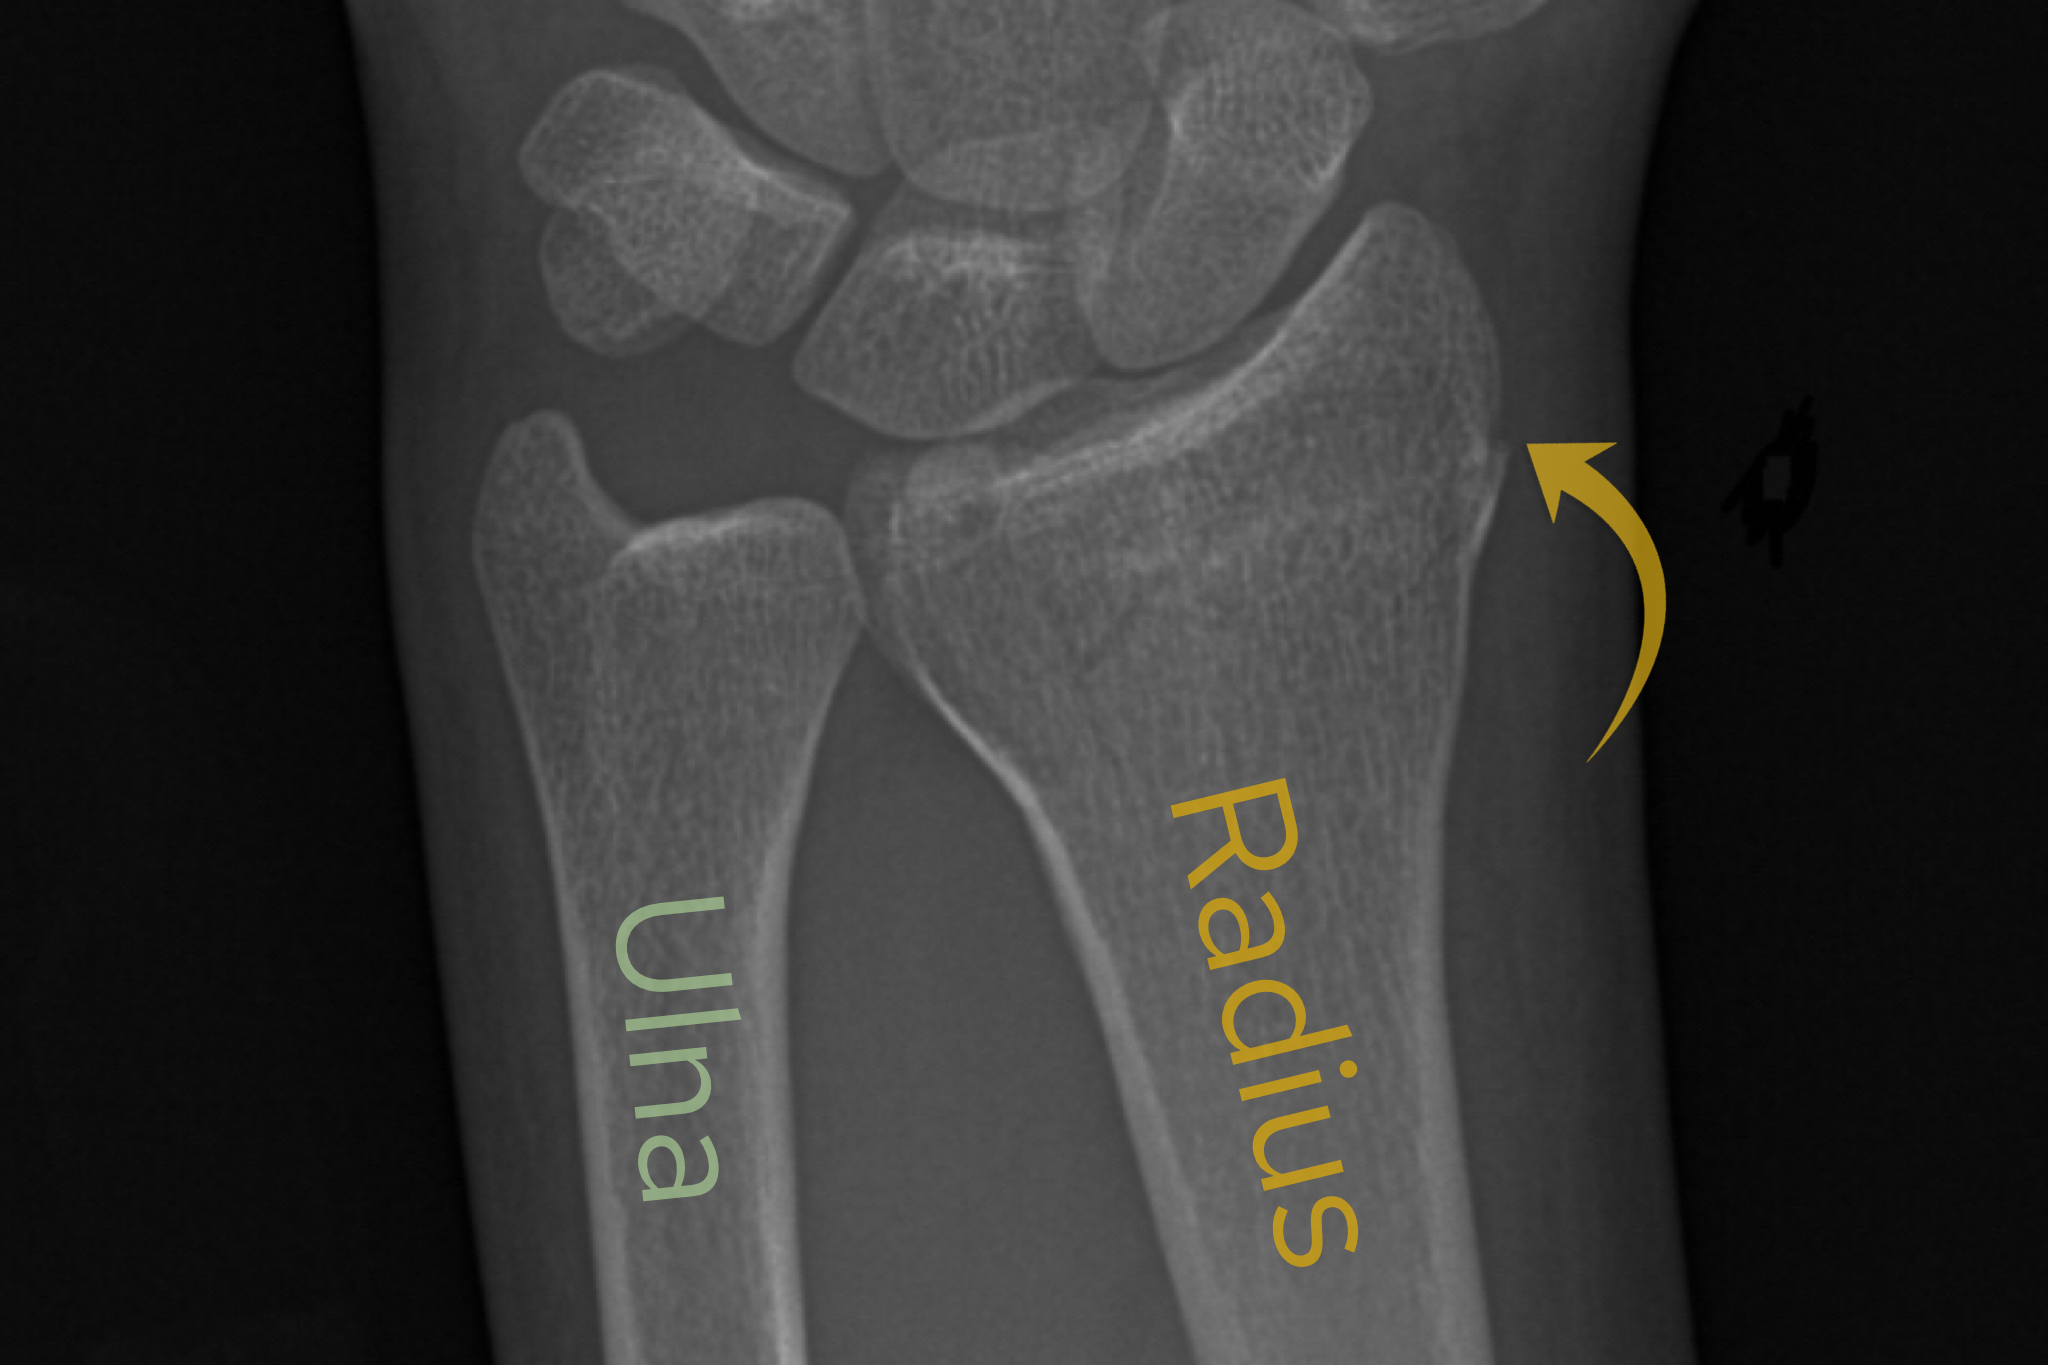

Case 9

A female in their 70s presents with wrist pain after a fall onto an outstretched hand (FOOSH). Assess the following wrist X-Ray. What is the most likely diagnosis?

Choose from one of the following options: